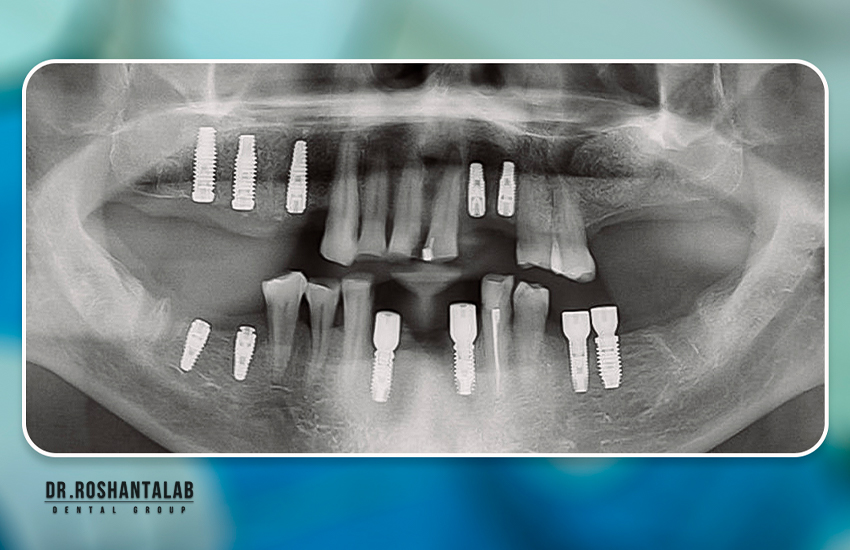

زمان بهبودی پس از جراحی ایمپلنت دندان بسته به مورد فردی، تعداد دندانهای آسیبدیده هر بیمار و مهمتر از همه، نحوه مدیریت دوران نقاهت میتواند متفاوت باشد. ۹۹% موارد تحت بی حسی موضعی در جراحی دندان و گاهی همراه با آرامبخشی داخل وریدی یا خوراکی درمان و ایمپلنت کاشته می شود.

در مورد کاشت ایمپلنت دندانی ساده، با پیوند کم یا بدون پیوند (به عنوان مثال برای جایگزینی یک دندان عقب از دست رفته، یا ایمپلنت فوری برای جایگزینی دندان از کار افتاده) ناراحتی یا تورم پس از عمل کم است یا اصلاً وجود ندارد.

هیچ زمان استانداردی برای بهبودی و زمان ریکاوری بعد از ایمپلنت وجود ندارد زیرا شرایط دهان و دندان هر بیمار بر این روش تأثیر می گذارد. عوامل زیر ممکن است بر زمان بهبودی شما تأثیر بگذارند:

- تعداد کل دندان های کشیده شده و تحت درمان

- سلامت استخوان های شما (اگر بیمار نیاز به پیوند استخوان داشته باشد)